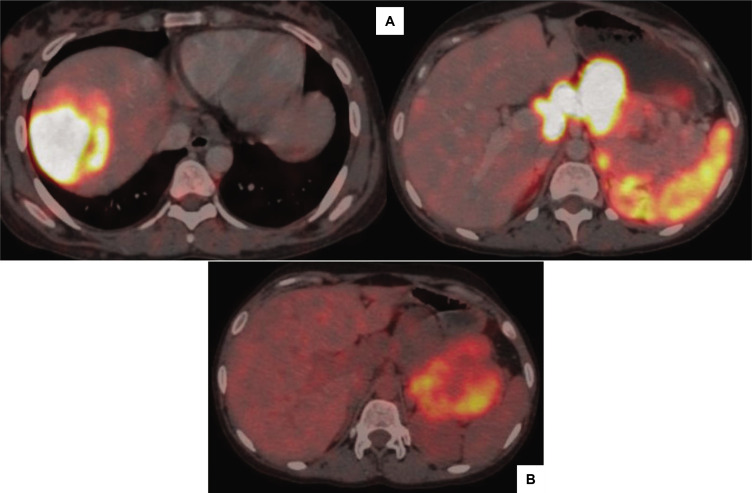

A 25-year-old woman presented with metastatic pancreatic neuroendocrine tumor with carcinoid syndrome. She was refractory to octreotide and did not respond well to chemotherapy. Although surgical debulking remains the primary approach for managing these tumours, it entails inherent risks, including potentially exacerbating carcinoid syndrome. We strategically delivered the one Peptide Receptor Radionuclide Therapy cycle before tumor debulking, a decision that yielded a remarkable response, stabilizing her condition.